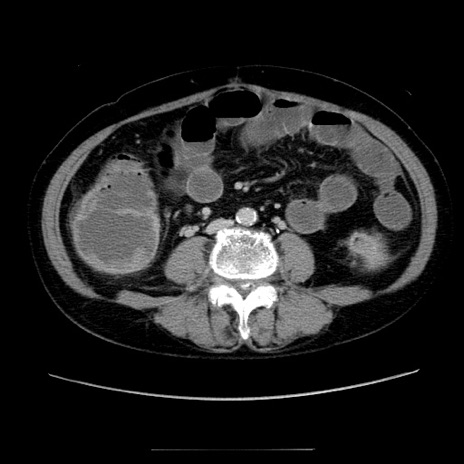

症例5(横断像)

【症例】70歳代女性

【主訴】お腹が張る

【現病歴】1週間くらい前から腹部膨満の自覚あり。昨日夜から増悪したため、本日救急外来受診。

【身体所見】意識清明、BT 36.5℃、BP 165/106mmHg、HR 80bpm、SpO2 98%、腹部:膨満、軟、自発痛・圧痛なし、触診にて不快感あり、腸蠕動音:減弱

【データ】WBC 12600、CRP 1.04